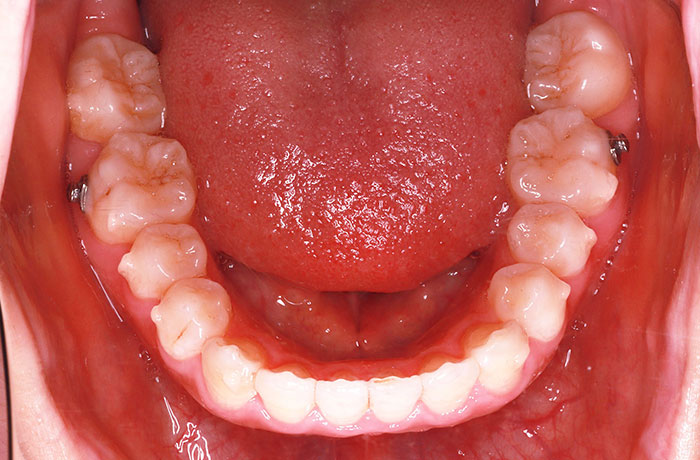

K様

治療前

年齢 27歳

性別 女性

治療名称 マウスピース型カスタムメイド矯正歯科装置(インビザライン)・コンプリヘンシブパッケージ(フルパッケージ)

総額治療費用 770,000円(税込10%) 金額備考 精密検査料・診断料 33,000円(税込10%)

治療期間 1年11か月 通院頻度など 40日ごと

1枚につき10日装着を指示しました。

治療内容

患者の症状 上顎前歯の前突、八重歯

治療方法 上下左右の第一小臼歯抜歯で、マウスピース型カスタムメイド矯正歯科装置による矯正

治療結果 上顎前歯の前突、八重歯が改善されました。

歯並びをより良くするために追加でアライナーを発注しました。

リスク/副作用 決められた時間装着する必要があります。